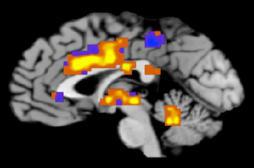

alzheimer